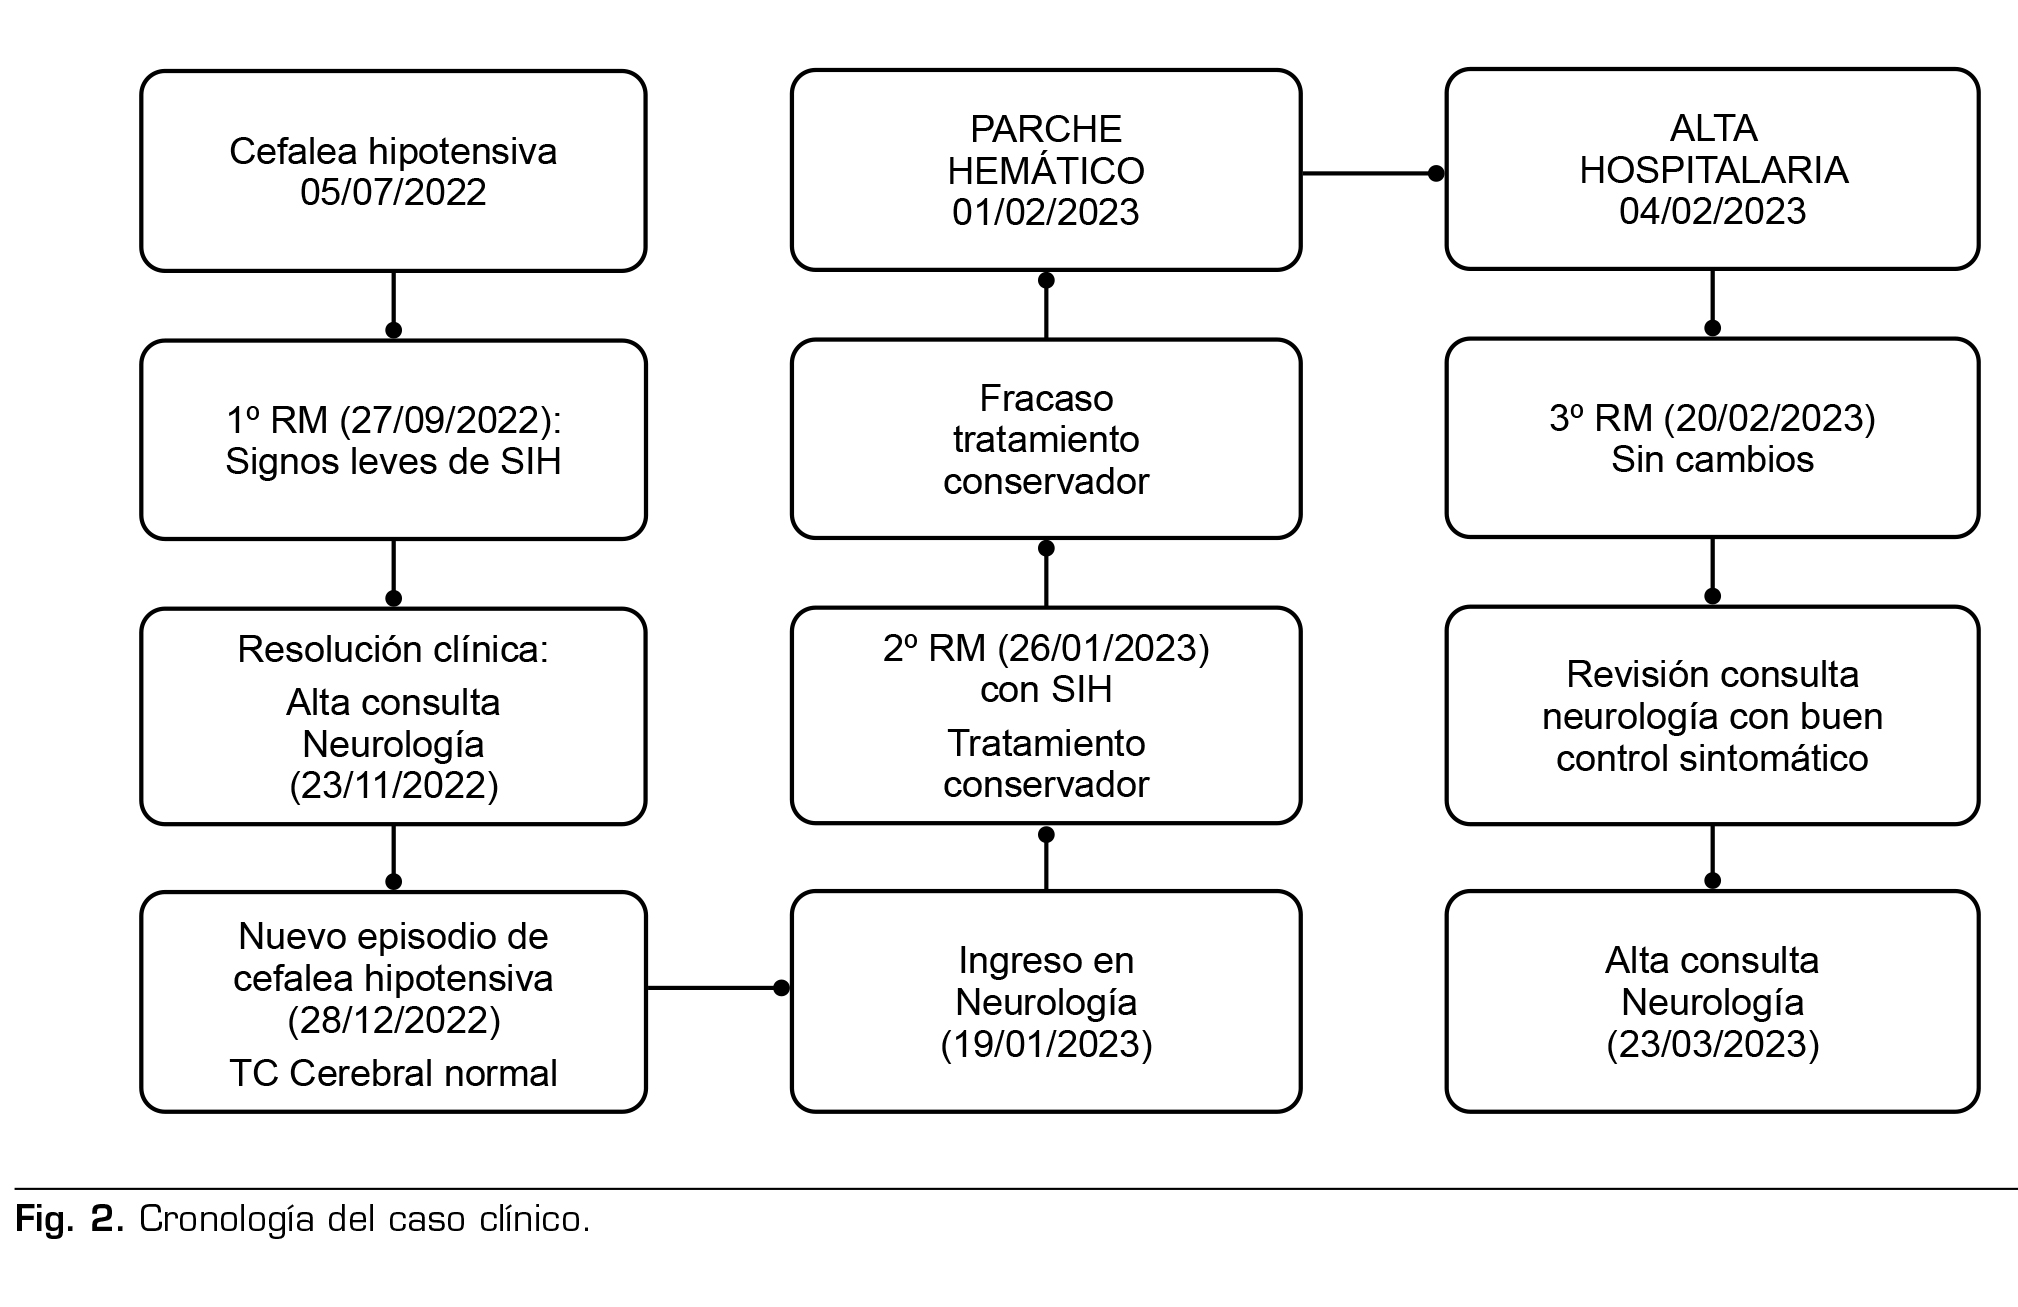

La paciente refería un episodio similar 6 meses antes, que se resolvió de manera espontánea al cabo de un mes y medio, pero que motivó 2 ingresos en urgencias. La tomografía computarizada cerebral fue normal, la sintomatología mejoró con analgésicos por vía intravenosa y fue derivada a su domicilio en las 2 ocasiones. Se continuó el seguimiento de forma ambulatoria y debido a la persistencia de síntomas leves se solicitó una RM cerebral con contraste, que objetivó hallazgos sugestivos de síndrome de hipotensión intracraneal, sin colecciones subdurales ni realces anómalos. La paciente tuvo una evolución favorable, con desaparición completa de la clínica con el tratamiento analgésico pautado (paracetamol, dexketoprofeno y amitriptilina), y se le dio el alta de consultas externas de Neurología.

La exploración neurológica al ingreso era normal, eutímica, con una puntuación en la Escala Visual Analógica (EVA) de 10. Unos días después del ingreso, con el tratamiento pautado refería un EVA de 4.

Pruebas complementarias: tomografía computarizada cerebral y analítica normales. RM cerebral y medular: signos de hipotensión intracraneal con engrosamiento dural y pequeñas colecciones laminares en convexidad frontoparietal, colecciones probablemente epidurales en la porción anterior cervical baja y en la región posterior a nivel dorsolumbar (Figura 1).

Tras el diagnóstico de cefalea secundaria a SIH, con clínica grave que no mejoró tras 10 días de tratamiento conservador, se contactó con la Unidad del Dolor para la realización de parche hemático lumbar.

No se había podido demostrar la existencia de fuga de LCR, pero la presencia de una colección líquida de 57 mm de longitud por delante de la columna anterior del LCR en los segmentos C6-T2, una colección epidural posterior desde T1 hasta T7, y las colecciones en la convexidad frontoparietal, sugerían la localización de las probables fugas, y decidimos realizar un parche hemático no dirigido.

Dada la sintomatología tan invalidante de la paciente, decidimos llevar a cabo el parche hemático vía caudal, para minimizar la posibilidad de provocar una nueva fuga de LCR por punción accidental de la duramadre que empeorara la clínica.

La técnica se realizó en el quirófano, con control por fluoroscopia, en decúbito prono, con aguja de Tuohy 18 G, e introducción del catéter para intentar llegar al espacio epidural lumbar. Tras comprobar con contraste yodado la localización de la punta del catéter (central y a nivel de L4-L5), inyectamos 20 ml de sangre autóloga extraída en el mismo momento, bajo medidas de estricta esterilidad, sin objetivarse complicaciones inmediatas. La paciente no refirió ninguna molestia durante la técnica.

La paciente permaneció en decúbito supino, se levantó a las 6 h aproximadamente durante un corto espacio de tiempo, sin referir cefalea. Inició la deambulación al día siguiente, sin cefalea ni ningún síntoma asociado. Como única incidencia, la paciente refirió una ligera sensación de tirantez cervical posterior con la flexión del cuello que mejoraba con la hiperextensión cervical, con un EVA de 1.

Fue dada de alta a las 72 h del procedimiento totalmente asintomática, 15 días después del ingreso.

En el seguimiento posterior desde consultas externas, se constataron algunos episodios de cervicalgia moderada y de cefalea leve, tolerable con el tratamiento analgésico oral (paracetamol y antiinflamatorios no esteroideos). Se repitió la RM cerebral un mes después del alta, que no mostró cambios. Debido a la persistencia de clínica leve a pesar del tratamiento, se planteó la realización de un mieloTAC, pero este no llegó a realizarse por mejoría progresiva de la clínica y se mantuvo una actitud expectante.

En la última revisión (3 meses después) constaba que no había vuelto a tener cervicalgia y cefalea. La paciente está asintomática en el momento actual y lleva una vida completamente normal (Figura 2).